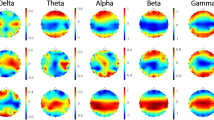

SampEn of the left middle occipital gyrus (MOG. L), the right middle occipital gyrus (MOG. R), the right inferior occipital gyrus (IOG. R), the left superior occipital gyrus (SOG. L), and the right rolandic operculum (ROL. R) in the patients is significantly higher than that in the controls. The color bar represents the p value. After FDR controls, regions of interest in the visual recognition network with p values below 0.0179 are considered to be significant, whereas regions of interest in the auditory network with p values below 0.0083 are deemed to be significant. (Color figure online)